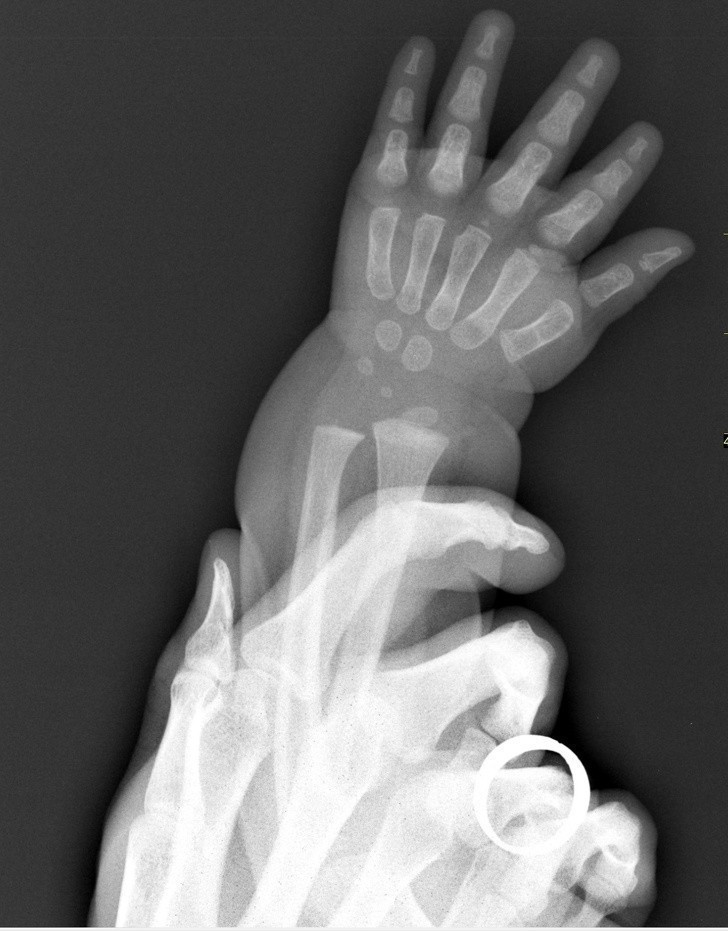

10. Porównanie dłoni dziecka i osoby dorosłej